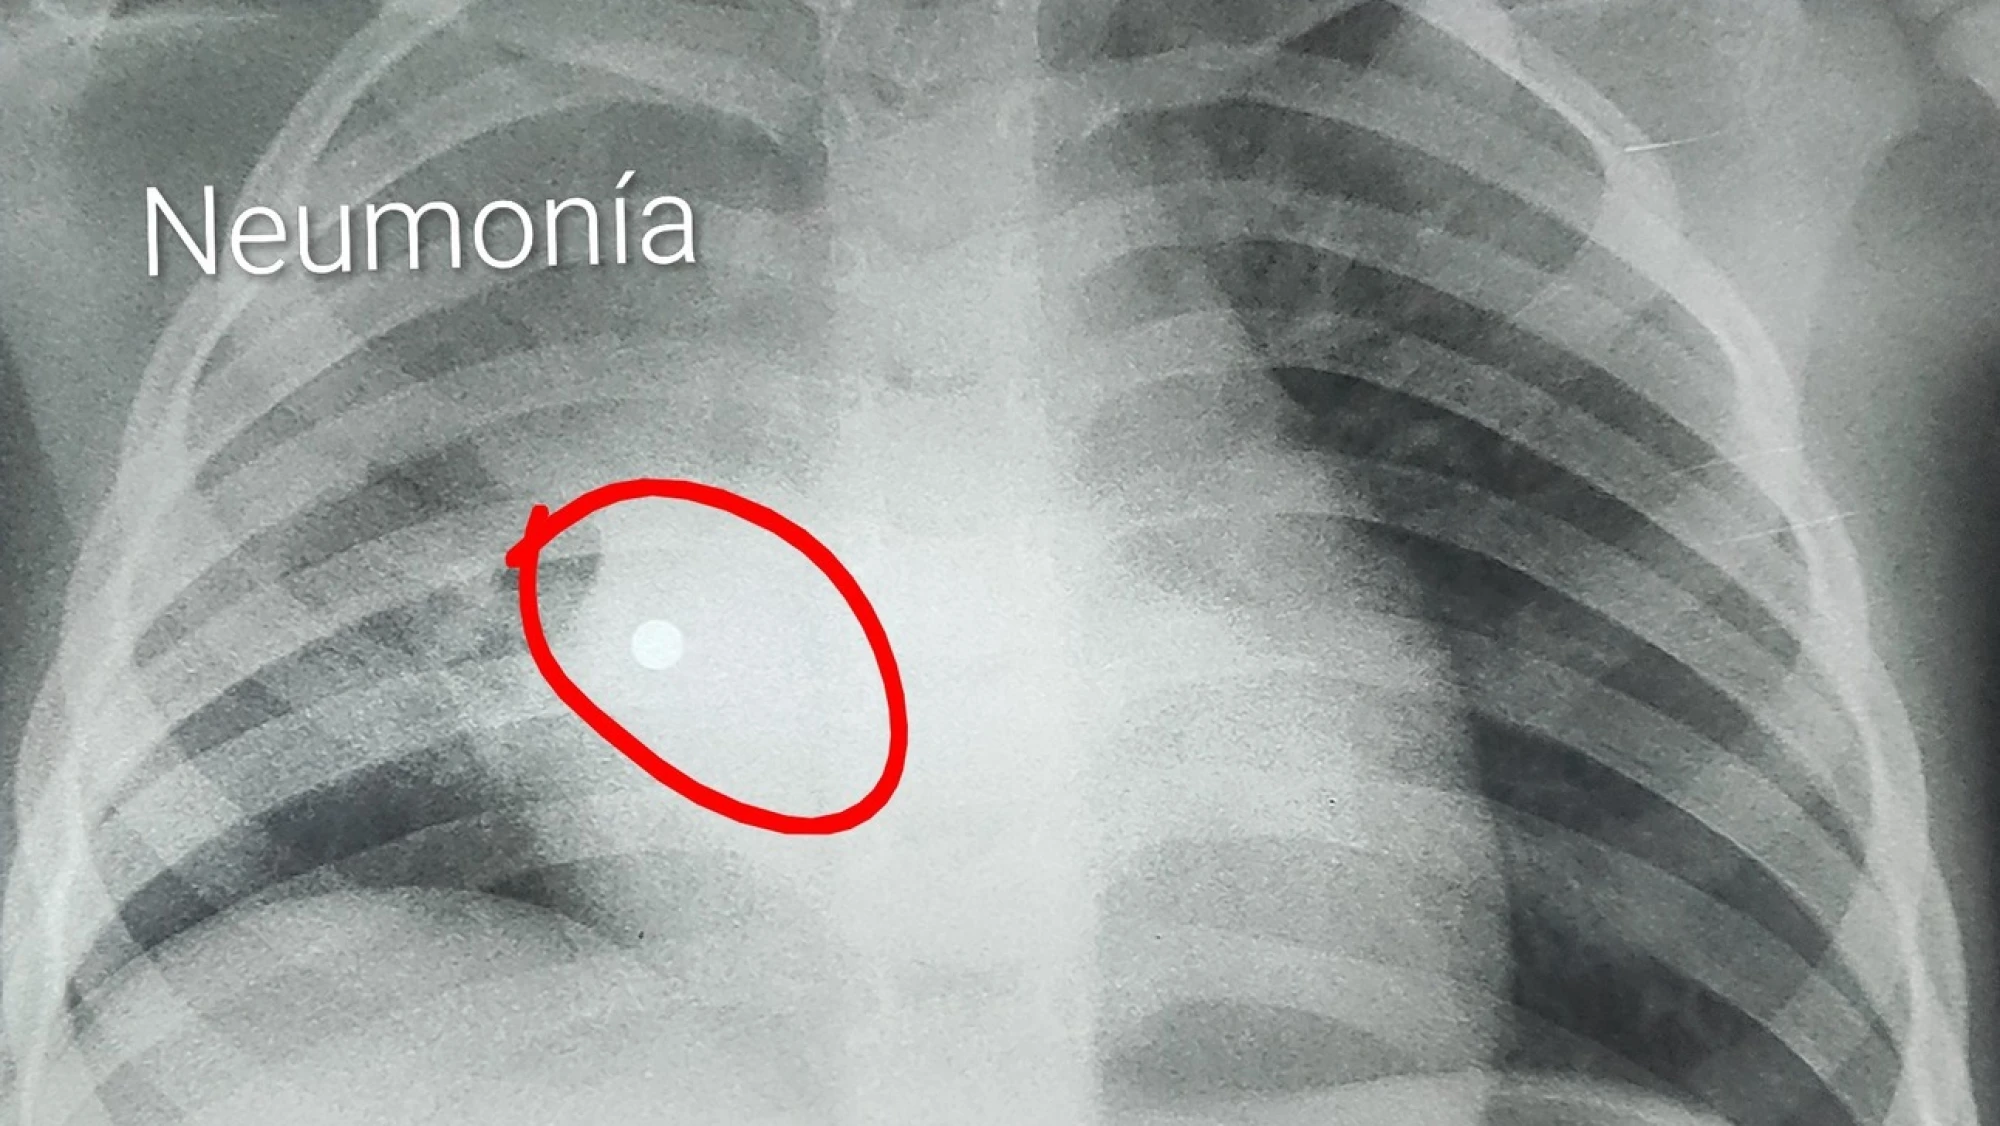

Cuatro de las perlas fueron al aparato digestivo, pero una tomó un camino que pudo ser fatal: se metió al pulmón, provocándole una neumonía grave que obligó a intubarla de urgencia en el Hospital de Trauma, en principio. Luego, la niña fue derivada al INERAM, y quedó a cargo del Dr. Morínigo y el equipo médico.

“Al ingresar observo pus en todos los bronquios y alláaa en el fondo de la base del pulmón la perla alojada”, explicó en sus redes sociales.